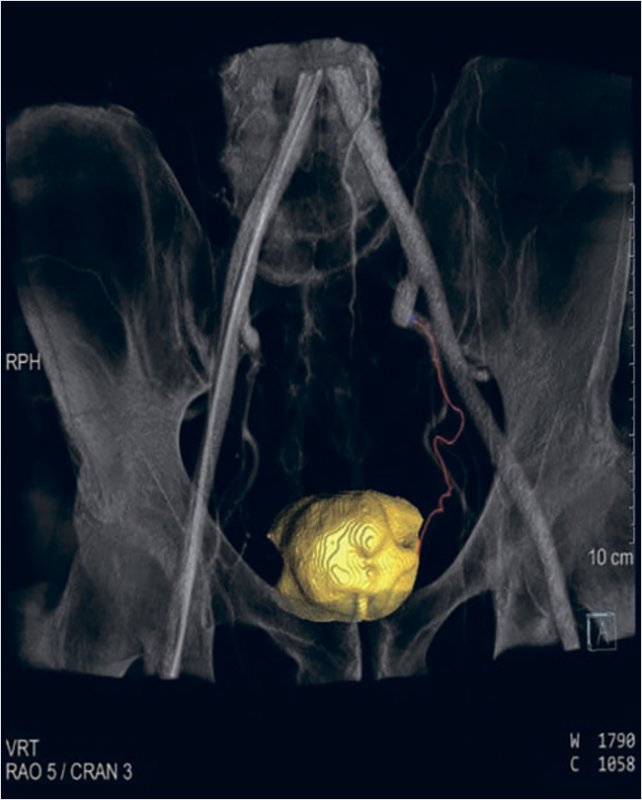

Рисунок 4. Селективная катетеризация простатической артерии слева. Ангиография простатической артерии слева до эмболизации

Затем была выполнена успешная окклюзия артерий с использованием микросфер (размером 100–300 мкм) до полного стаза контраста в дистальных сегментах простатических артерий (рис. 6). Дополнительных источников кровоснабжения простаты не было выявлено. Время вмешательства составило 75 мин. Доза лучевой нагрузки при проведении вмешательства составила 871 mGy. Объем введенного контрастного препарата равнялся 150 мл.

Рисунок 6. Ангиография простатической артерии слева после эмболизации